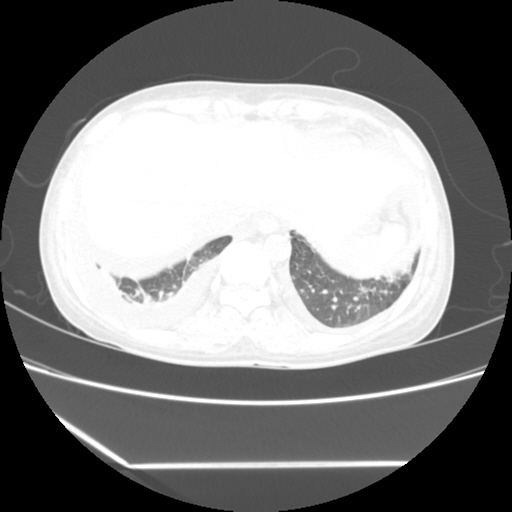

(HRCT)CT-Scan investigation done on 19Aug15 :

Series1